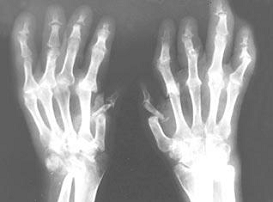

Суставной синдром: процесс симметричный с поражением дистальных фаланг кистей и стоп. Кожа отечная, напряженная, синюшно-багрового цвета, горячая на ощупь. Отмечается болезненность, деформация, ограничение подвижности, скованность суставов по утрам (рис. 3).

Рис.3 Деформация кистей

Рентгенография: вовлечение в процесс дистальных межфаланговых суставов. Признаки остеопороза, сужение суставных щелей, наличие кистовидных просветлений.

Признаки остеопороза, сужение суставных щелей, наличие кистовидных просветлений